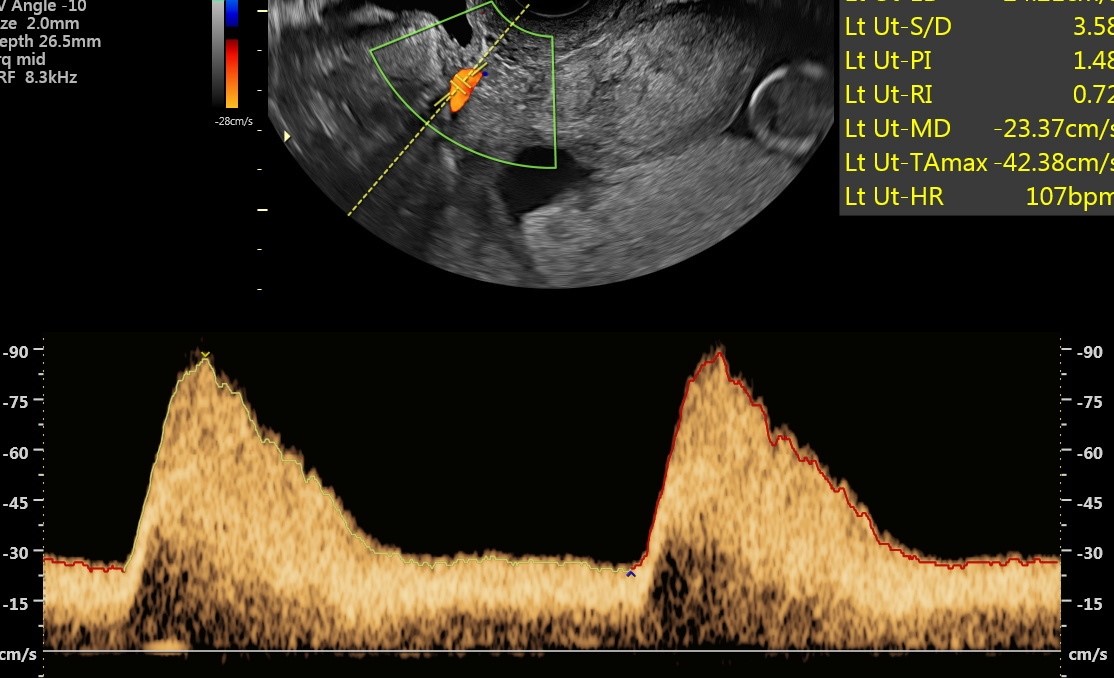

Nieprawidłowe przepływy w tętnicy macicznej w czasie ciąży, fot. USK-2

Kobietom objętym programem PRENATALPROJEKT wykonywane jest w 1. trymestrze badanie USG, mierzone jest ciśnienie oraz badane są trzy substancje, które pozwalają zdiagnozować funkcjonowanie łożyska i wykryć ww. patologie. Standardowe badania prenatalne obejmują badanie dwóch substancji i nie dają one wystarczająco miarodajnych i pewnych wyników co do prawidłowości funkcjonowania łożyska. W 2. trymestrze ciąży wykonywane jest już samo USG oraz badane ciśnienie. W przypadku wykrycia nieprawidłowości ciężarna zostaje objęta szczególną opieką i monitoringiem. W specjalnie utworzonej aplikacji, którą może pobrać na telefon i z której korzysta także jej ginekolog położnik, podaje mierzone kilka razy dziennie ciśnienie oraz wagę. Lekarz badań prenatalnych, biorący udział w programie decyduje o podjęciu leczenia. W przypadku niewydolności łożyska jest nim podanie odpowiedniej dawki aspiryny. Kobieta przyjmuje ją pod kontrolą lekarza do 36. tygodnia ciąży, który określany jest jako bezpieczny dla rozwoju dziecka, a rozwiązanie ciąży nie stanowi dla niego już takiego ryzyka.